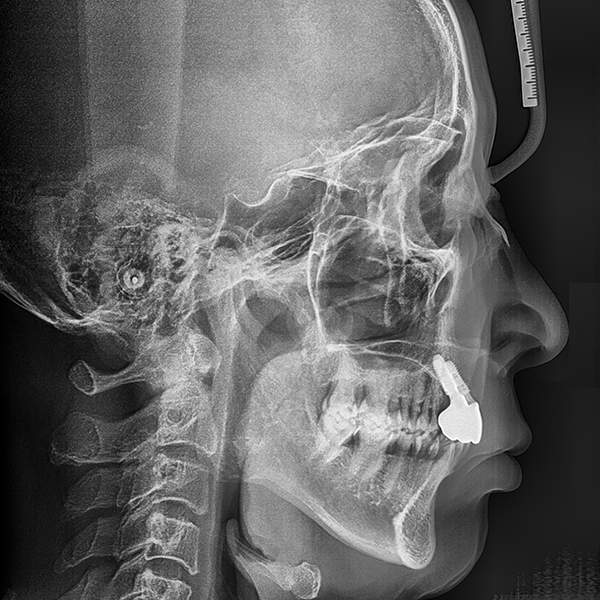

3. Тохиолдол.110 60-аад насны И*Гэ 2020-01-20 / 2020-3-21

Нэг өдрийн шүдний эмнэлэг

상악/앞니 부분 / 3개이하 / 뼈이식|고혈압

Тохиолдол.110 60-аад насны И*Гэ 2020-01-20 / 2020-3-21

Before Before

After After